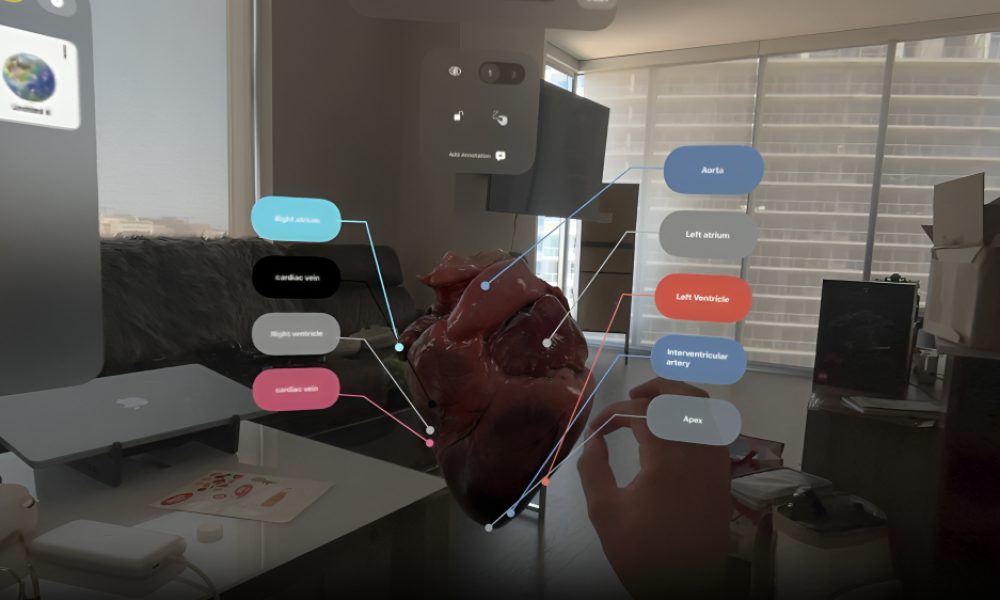

In an increasingly digital world, the ability to effectively communicate 3D…